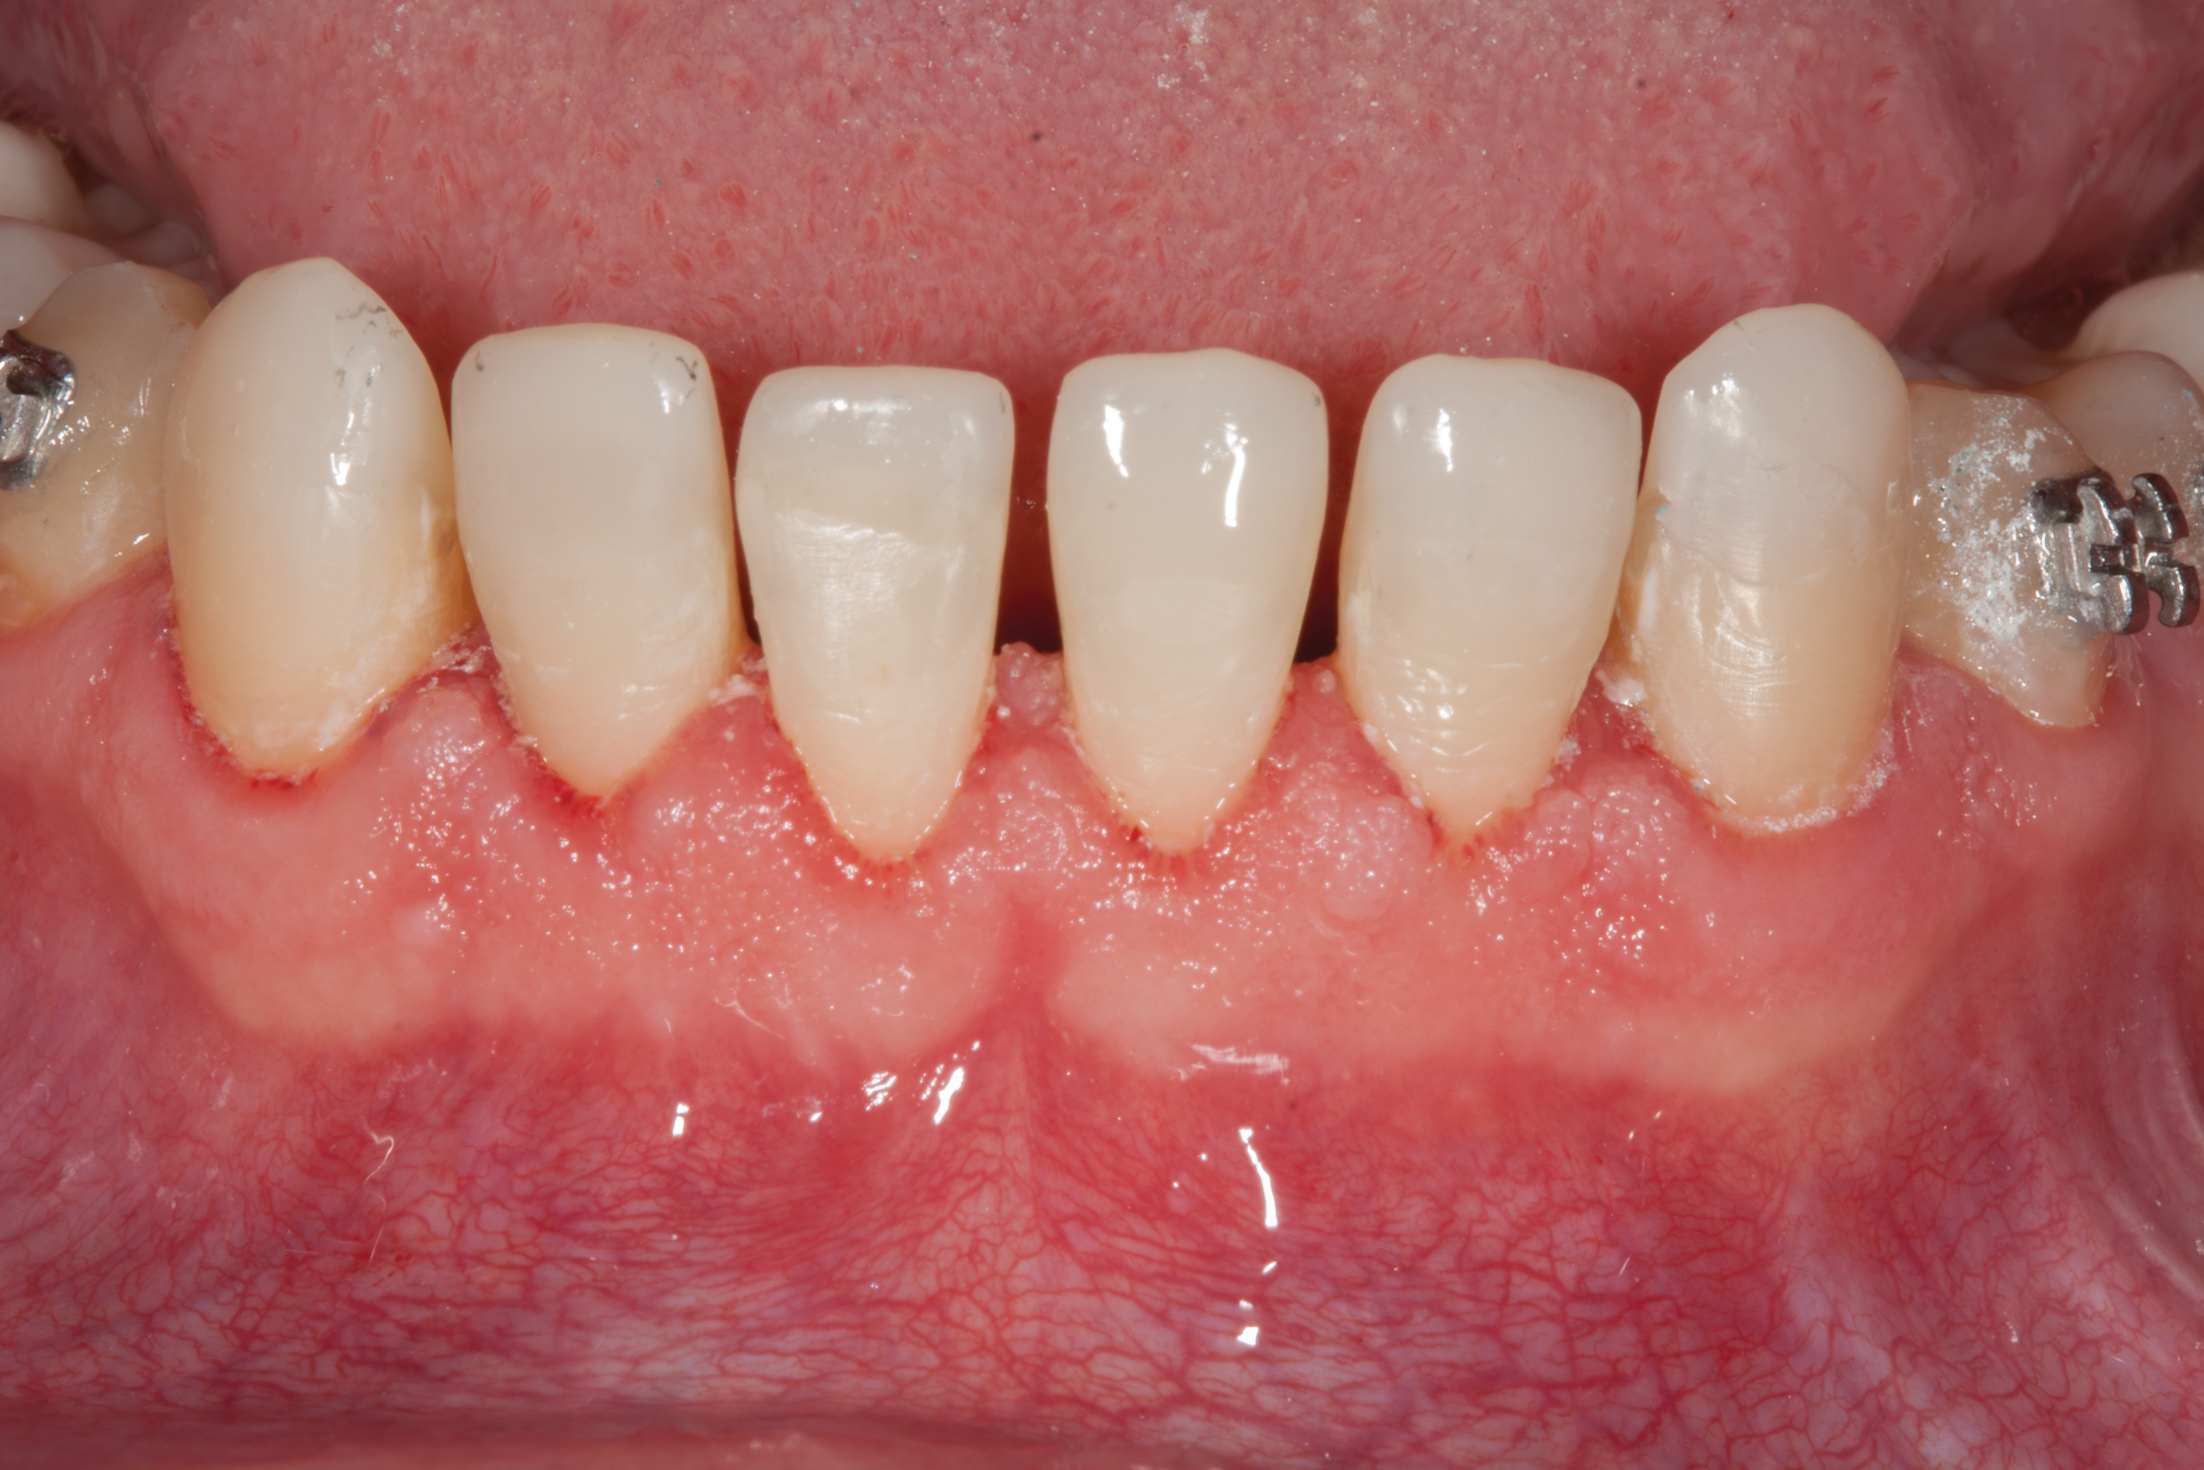

Fig 10. Corticocancellous particulate allograft positioned in the mandible to increase the orthodontic boundary conditions and provide an expanded envelope to reposition teeth.

Figure 10

Fig 11. Interim orthodontic phase and transitional bonding to be accomplished based on Bolton analysis now that overly sufficient space has been appropriated for the creation of proportionately correct mandibular incisors. Once transitional bonding is complete, orthodontic finishing will be performed and any remaining spaces closed.

Figure 11